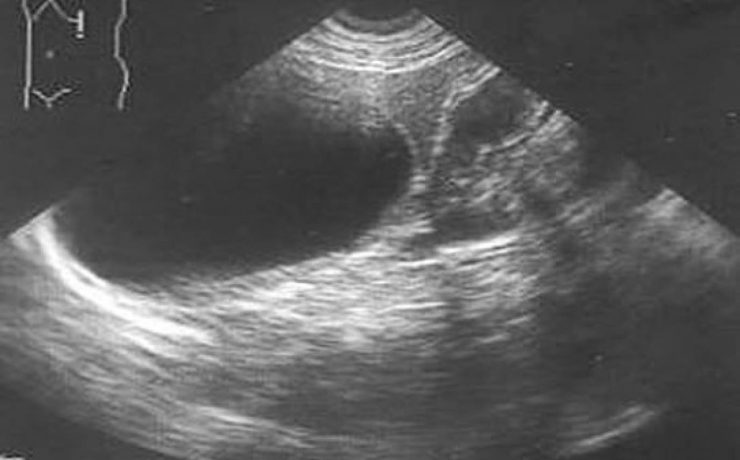

Existen alteraciones ováricas valorables por ecografía tratándose generalmente de alteraciones foliculares las cuales se presentan clínicamente como defectos en la maduración además del número de los mismos. Ecográficamente se diferencia el tamaño, el grosor capsular y su estroma puede estar aumentado e hiperecogénico. Otra patología son los quistes que